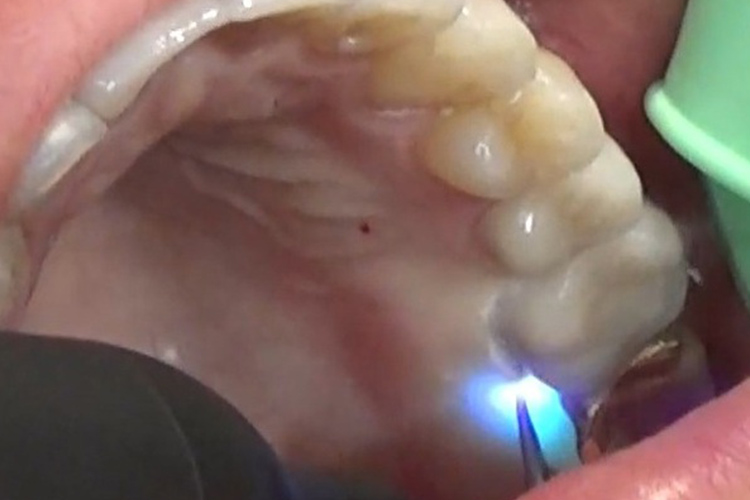

施術風景

深い歯周ポケットに青いレーザー光と過酸化水素水を照射し、患部を殺菌します。

深い歯周ポケットに青いレーザー光と過酸化水素水を照射し、患部を殺菌しています。